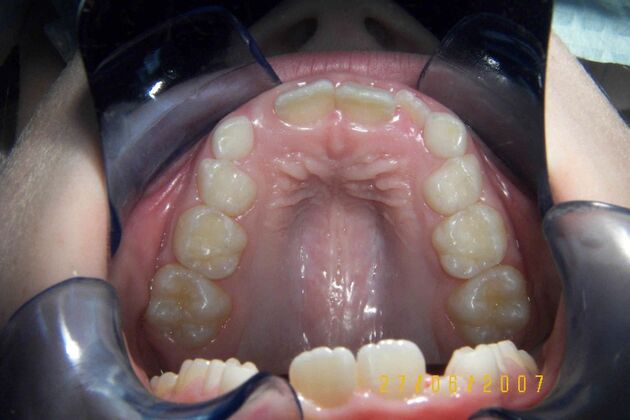

Patient is 9 years old and presents with 100% overbite and blocked out upper and lower lateral incisors. Both upper central incisors are palatally inclined causing a lack of space available for most anterior teeth. Advised her parents that she needs Phase I Interceptive Orthodontic treatment to provide room for all upper and lower front teeth. Phase I treatment was begun and finished, then began Phase II treatment shortly thereafter to finalize case. Removable retainer were fabricated for retention.